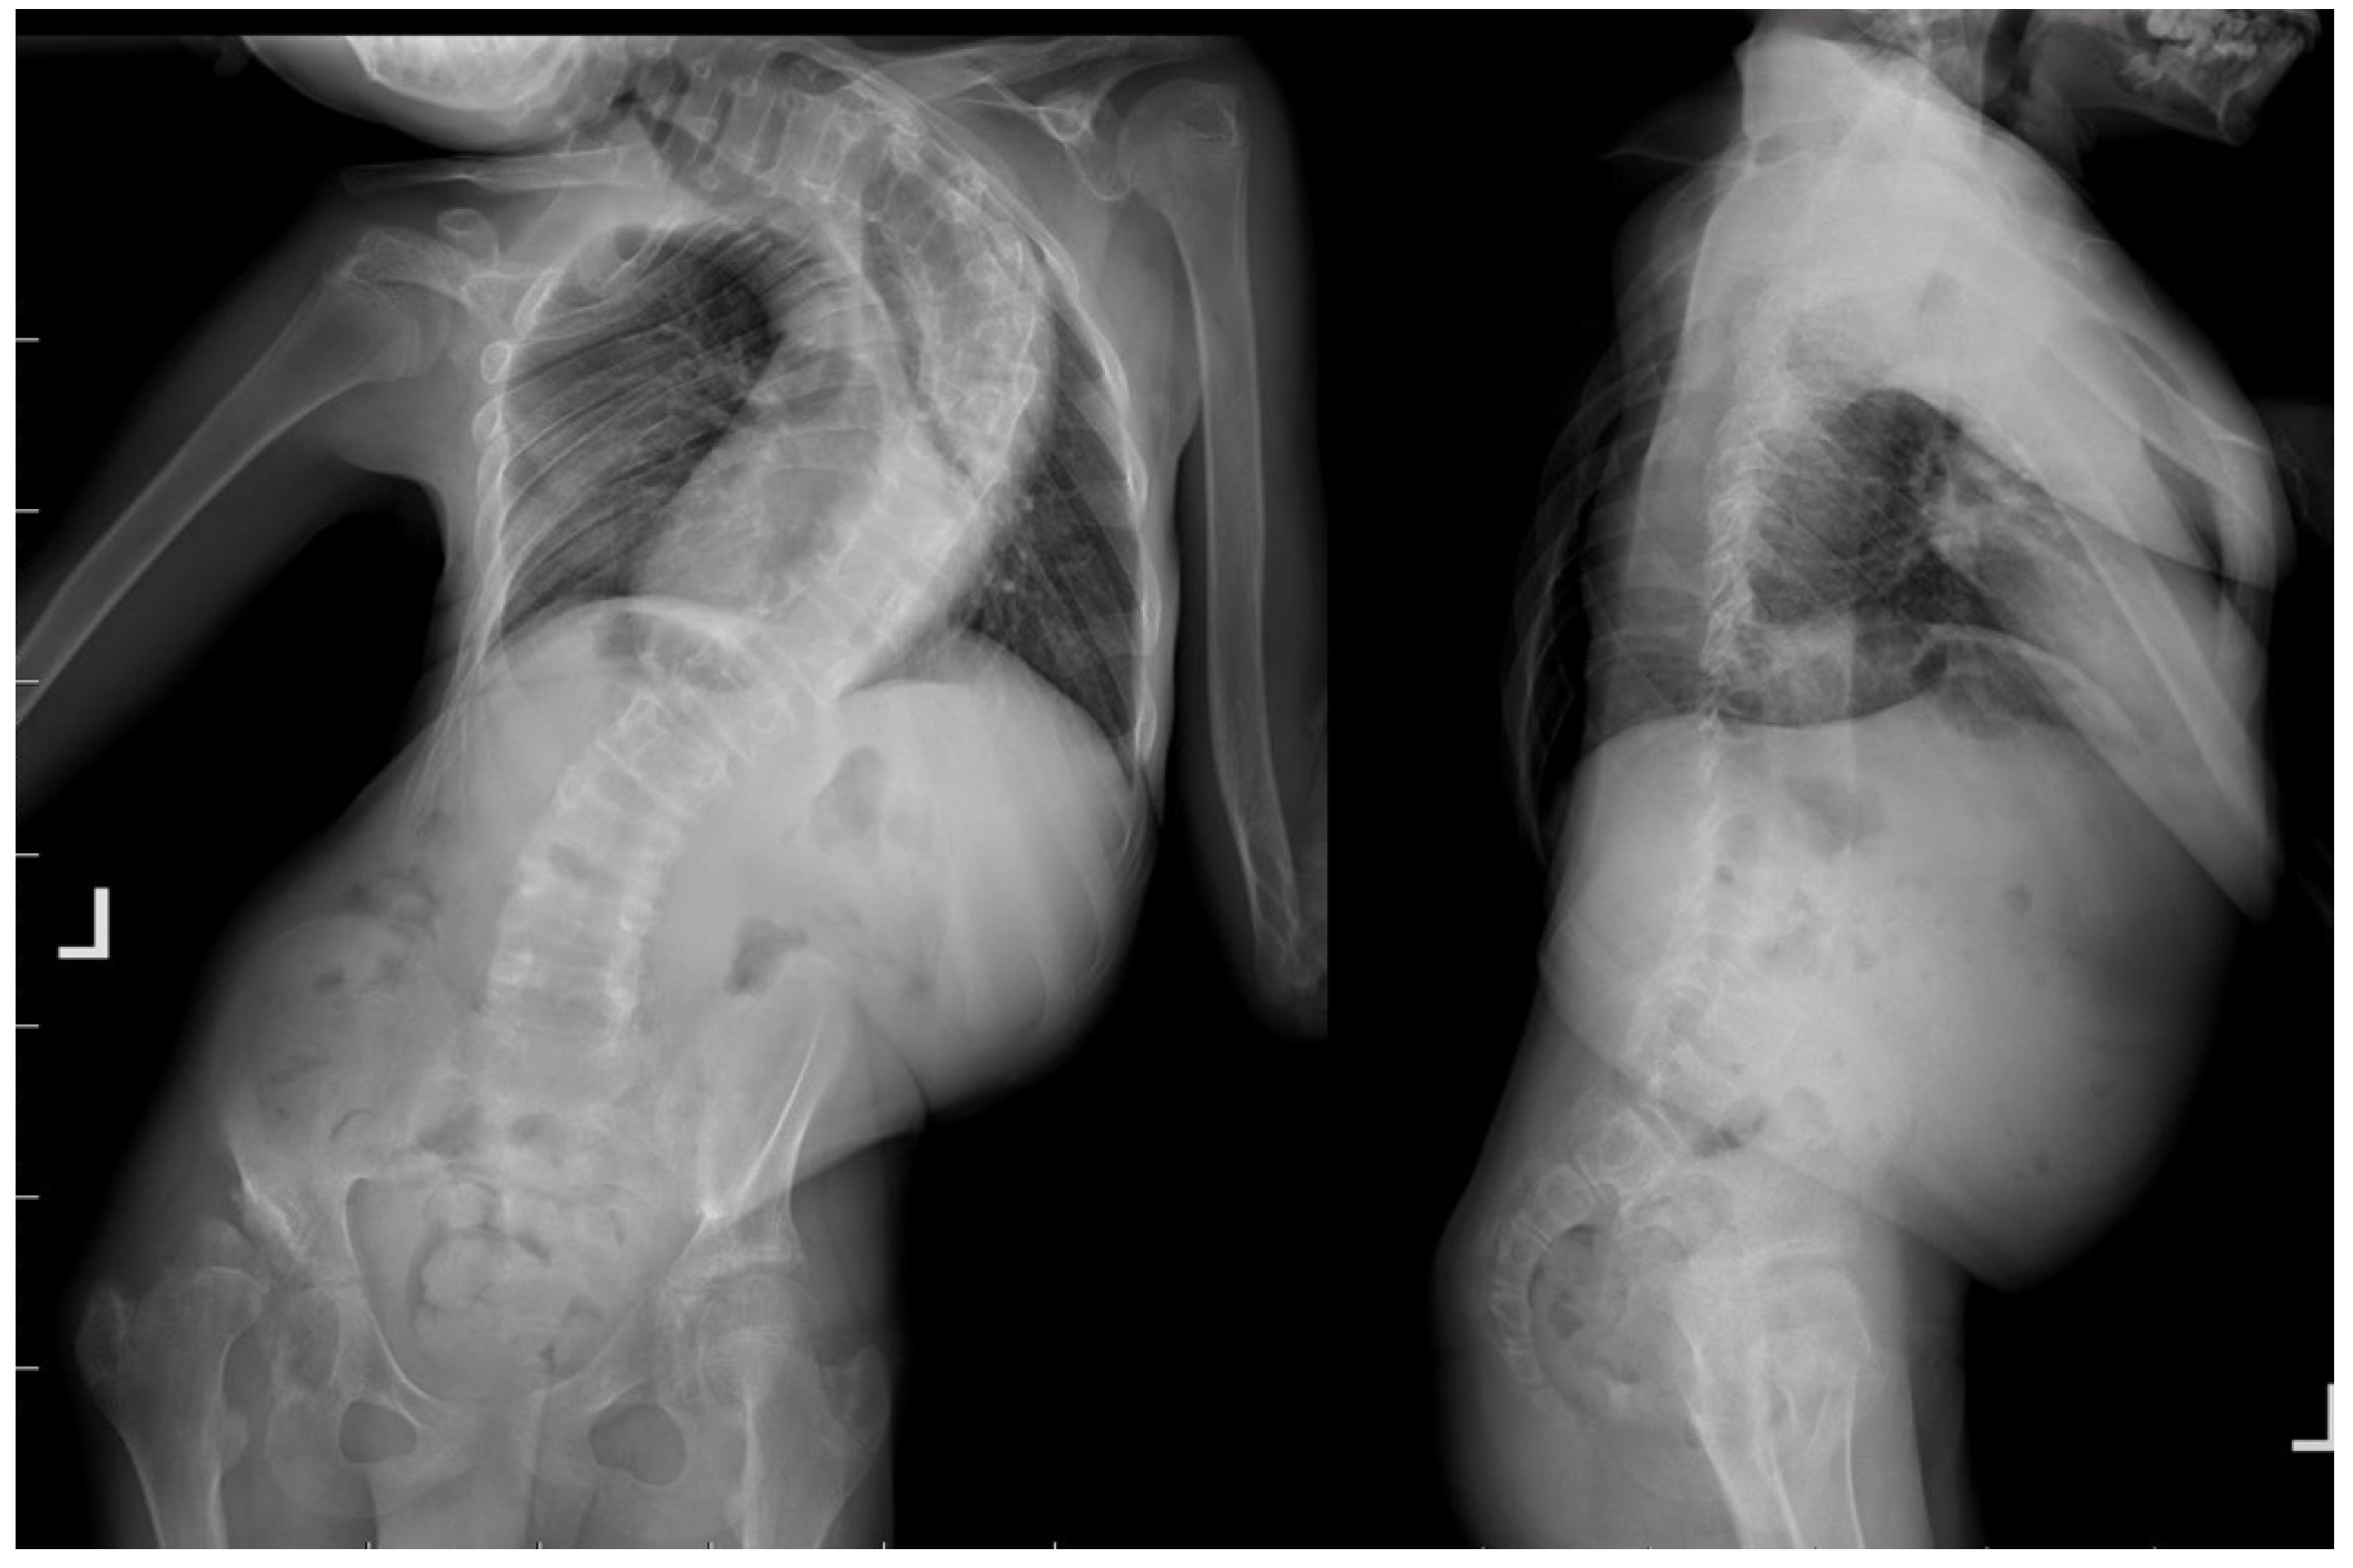

2. Case Presentation